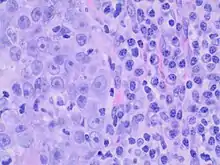

Medullary breast carcinoma is a rare type of breast cancer[1] that is characterized as a relatively circumscribed tumor [2] with pushing, rather than infiltrating, margins. It is histologically characterized as poorly differentiated cells with abundant cytoplasm and pleomorphic high grade vesicular nuclei.[3] It involves lymphocytic (a type of white blood cell) infiltration[4] in and around the tumor and can appear to be brown in appearance with necrosis and hemorrhage.[5] Prognosis is measured through staging but can often be treated successfully and has a better prognosis than other infiltrating breast carcinomas.

Criteria must be met through the Ridolfi criteria. Although there are other classifications for diagnosis, the Ridolfi criteria are the most commonly used. There must be histologic evidence of lymphoplasmacytic infiltration, noninvasive microscopic circumscription, greater than 75% syncytial growth pattern, and high-grade nuclei.[5] It is immunologically typically triple-negative, with negative estrogen receptors (ER), negative progesterone receptors (PR), and negative HER2/neu receptors.[3] There are also medullary breast carcinomas that are found to be estrogen receptors (ER) and/or progesterone receptor (PR) positive, making diagnosis less straightforward.